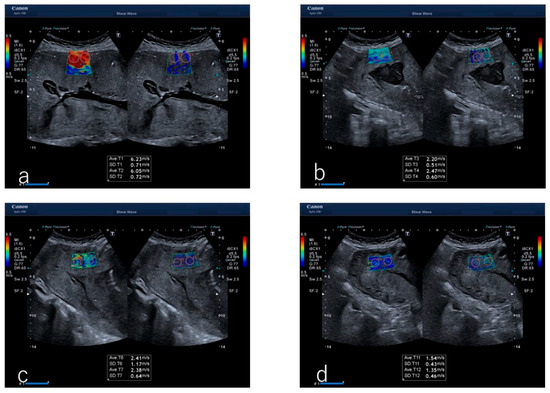

Figure 1. Image of ultrasound shear wave elastography during the third stage of labor in the case of a participant. (a) Immediately after infant delivery, (b) 240 s later, (c) 300 s later, and (d) 360 s after infant delivery.

SWE was performed using a 5.5 MHz convex probe (Aplio i700 PVI-475BX, Canon Medical Systems, Otawara, Japan) and analyzed using the manufacturer’s software V5.1. An author (Okuyama) intermittently measured the myometrial SWV transabdominally every 15 s from immediately after infant delivery to placental delivery (Figure 1). The ultrasound transducer was placed at the site between the upper quarter of the anterior wall of the uterus on a straight line connecting the maternal navel and pubic bone for probe placement. Irradiation was performed perpendicular to the anterior uterine wall. The region of interest for SWV measurement was set at 2 × 3 cm or 1 × 3 cm.